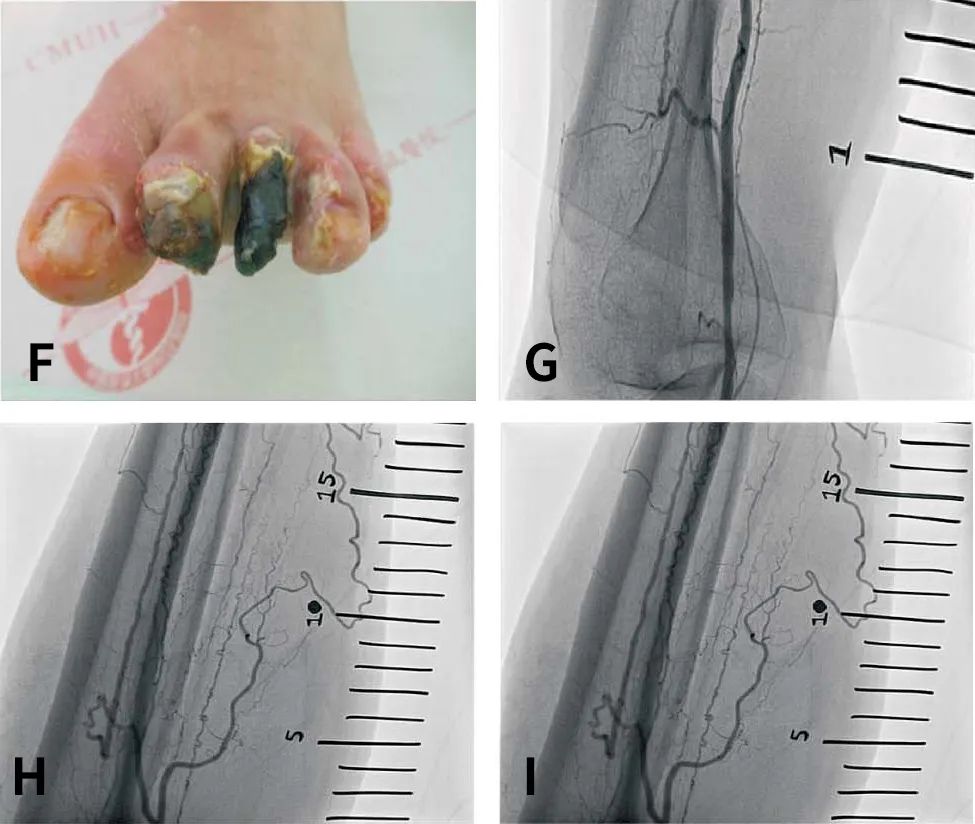

缺血的足趾出现干性坏疽改变,Rutherford分级为6级(图1F)。血管造影显示胫前动脉狭窄(图1G),胫后动脉和腓动脉慢性全闭塞(图1H),以及踝上水平的迂曲小侧支动脉和Buerger病典型的螺旋状血管改变(图1I)。

图1. 经皮深静脉动脉化术前的左足慢性创面及血管造影。